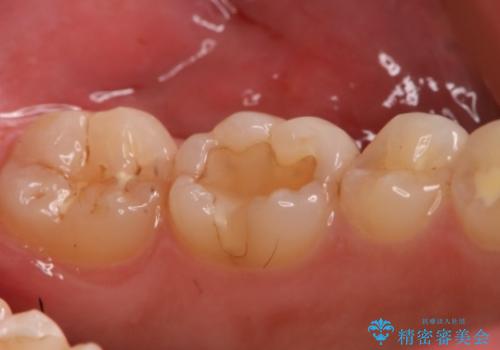

- 左下6番の治療のやり直しを希望し来院された患者様です。

保険の材料が劣化し段差や隙間ができてしまっている状態です。

自費の治療を希望されたため切削量・形態を考慮し、セラミックインレーでの治療を計画しました。

保険の材料と比較して、セラミックは劣化しにくく審美性も高い材料です。